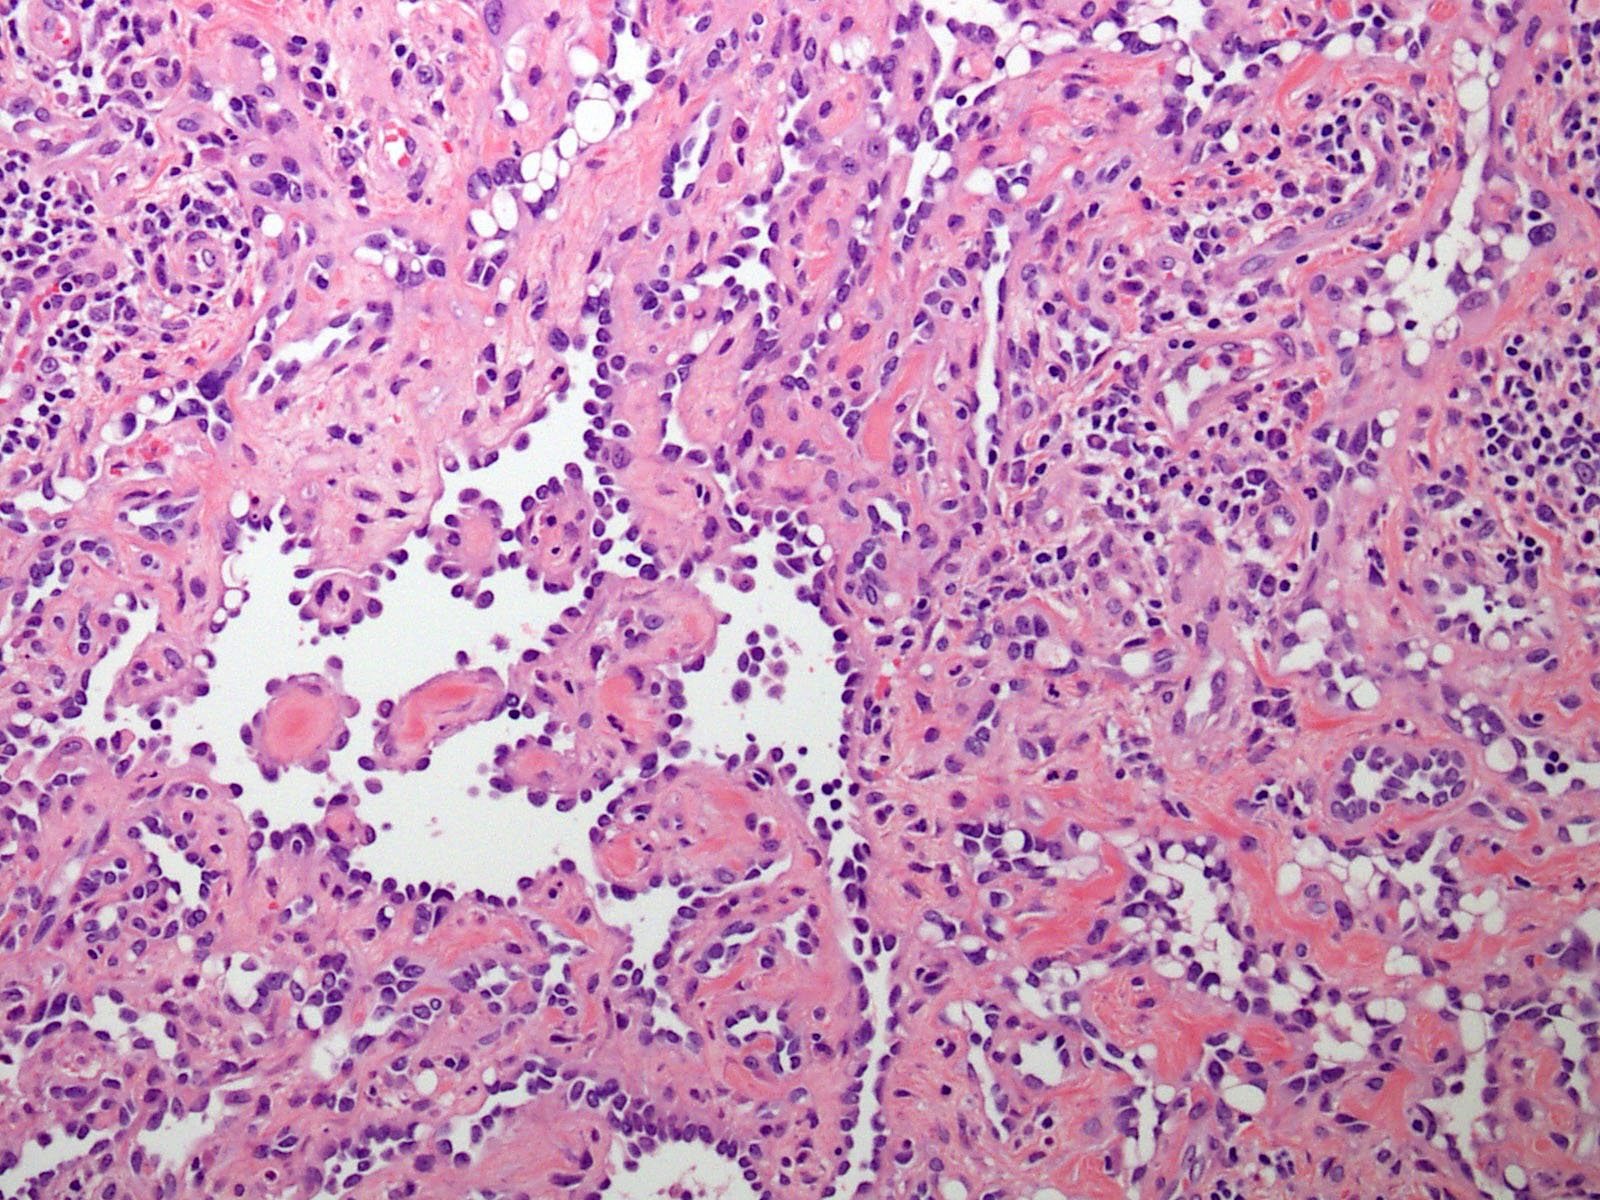

Microscopic (histologic) description

- Poorly circumscribed lesion, infiltrating dermis and subcutis with dissecting planes (Int J Clin Exp Pathol 2010;3:528)

- Composed of elongated arborizing vascular channels that resemble rete testis, hence the name

- Endothelial cells are bland with hobnailed hyperchromatic nuclei

- Nuclear atypia is not seen

- Mitotic figures are rare

- Lesional stroma is fibrotic and shows lymphoid infiltrate (J Med Case Rep 2021;15:69, Int J Clin Exp Pathol 2010;3:528)

- Occasional solid growth may be seen (Stockman: Diagnostic Pathology - Vascular, 1st Edition, 2015)

- In the dermis, vessels may become ectatic and lose retiform appearance

- Occasional cells with cytoplasmic lumina may be rarely seen (J Med Case Rep 2021;15:69)

- Occasionally, intraluminal papillary proliferation may be seen, resembling Dabska tumor (Hornick: Practical Soft Tissue Pathology - A Diagnostic Approach, 2nd Edition, 2018)

Microscopic (histologic) images